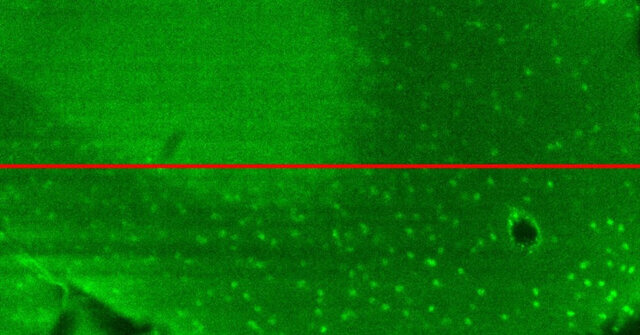

نورشناسی تطبیقی ​​هنگام اصلاح اعوجاج نوری رایج هنگام تصویربرداری از بافت‌های ضخیم مفید است. دانشمندان برای اینکه با این مشکل روبرو نشوند، معمولاً به یک میکروسکوپ سفارشی ساز نیاز دارند که شامل یک آینه قابل تغییر شکل است. با این حال، انجام این کار همیشه آسان نیست و زمان می‌برد.

از این رو محققان به فکر یافتن راه حلی برای این مشکل افتادند و با ابداع شیشه‌های هوشمند فوق‌العاده نازک که برای بهبود دید میکروسکوپ‌ها بدون شکستن خم می‌شوند، توانسته‌اند به خوبی این مانع را از سر راه دانشمندان بردارند.

این تیم یک تکه شیشه ایجاد کرده که بسیار نازک و قابل انعطاف است. لنز این دستگاه از یک ظرف شیشه‌ای به شکل دیسک که از مایع شفاف پر شده، تشکیل شده است و مجموعه‌ای از ۱۸ محرک مکانیکی روی لبه شیشه قرار دارد که توسط یک رایانه کنترل می‌شوند تا شیشه را به دلخواه، شکل داده و خم کنند.